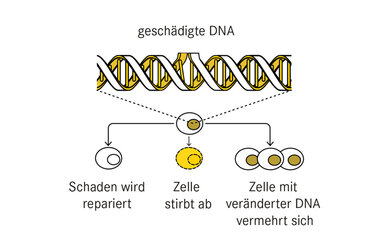

Wie schadet ionisierende Strahlung dem Menschen?

© W&B/Astrid Zacharias

Radioaktive Strahlung schädigt Körperzellen, indem sie das Erbgut (DNA) verändert oder zerstört. Bei sehr hohen Dosen (über 500 mSv) treten akute Schäden auf, die unmittelbar zu Krankheiten oder sogar zum Tod führen können. Niedrigere Strahlendosen erhöhen langfristig das Risiko, dass einzelne geschädigte Zellen sich vermehren und Krebs verursachen.